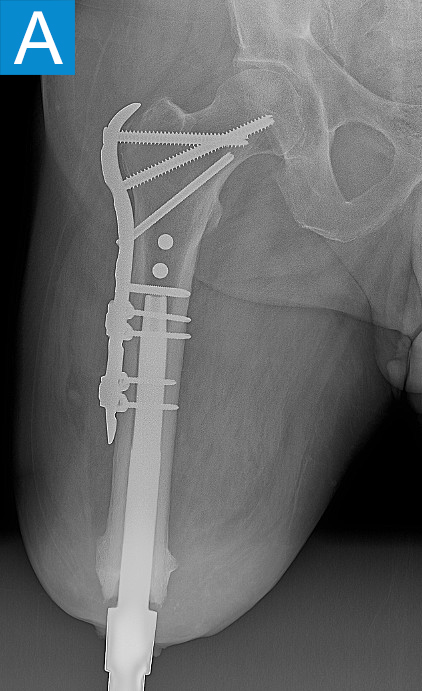

He started progressively loading the implant at 2 weeks and received his full prosthetic leg with simple hinged knee at 6 weeks. At 3 months he no longer used assist devices and at 3.5 months his prosthesis was changed to a microprocessor-controlled knee. Shortly after receiving the new knee, he stumbled stepping over a ledge and fell, sustaining a subtrochanteric proximal femur fracture (Figure 2b). The fracture extended to the tip of the implant, which remained stable in the bone. He underwent open reduction and internal fixation of the femur fracture with a proximal locking plate (Figure 2c). He did not wear the prosthetic leg for 10 weeks, when he began gradually loading the femur. He resumed full weightbearing without assistive devices about 6 weeks later.

Figure 2. Postoperative X-rays shows (A) a femoral osseointegration implant; (B) a subtrochanteric proximal fracture; (C) the femur fracture repaired by open reduction and internal fixation with a proximal locking plate.

Periprosthetic fracture around osseointegrated stems is not surprising, given the stress concentration that occurs proximally to the stem. The incidence is around 5% and mostly due to falls [2]. The stems themselves are nearly always stable in the bone because the osseointegration is robust. This was true in this patient despite less than 4 months of integration time. Thus, the stem can nearly always be maintained and the fracture fixation follows familiar principles. Many periarticular plating options now exist for the femur so that screws can be placed into the diaphysis around the stem to achieve proximal fixation. With stable fixation the healing is usually routine because the forces on the fracture are minimal without the prosthesis attached. Patients usually go back to their prior level of function once healed [2].